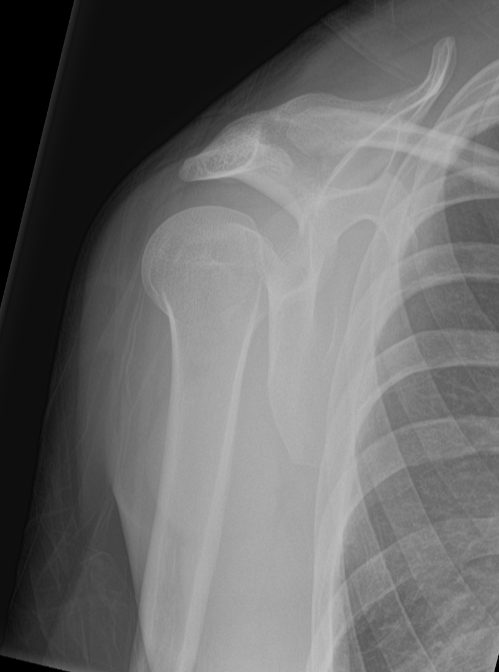

Posterior glenohumeral dislocation (Lightbulb sign)